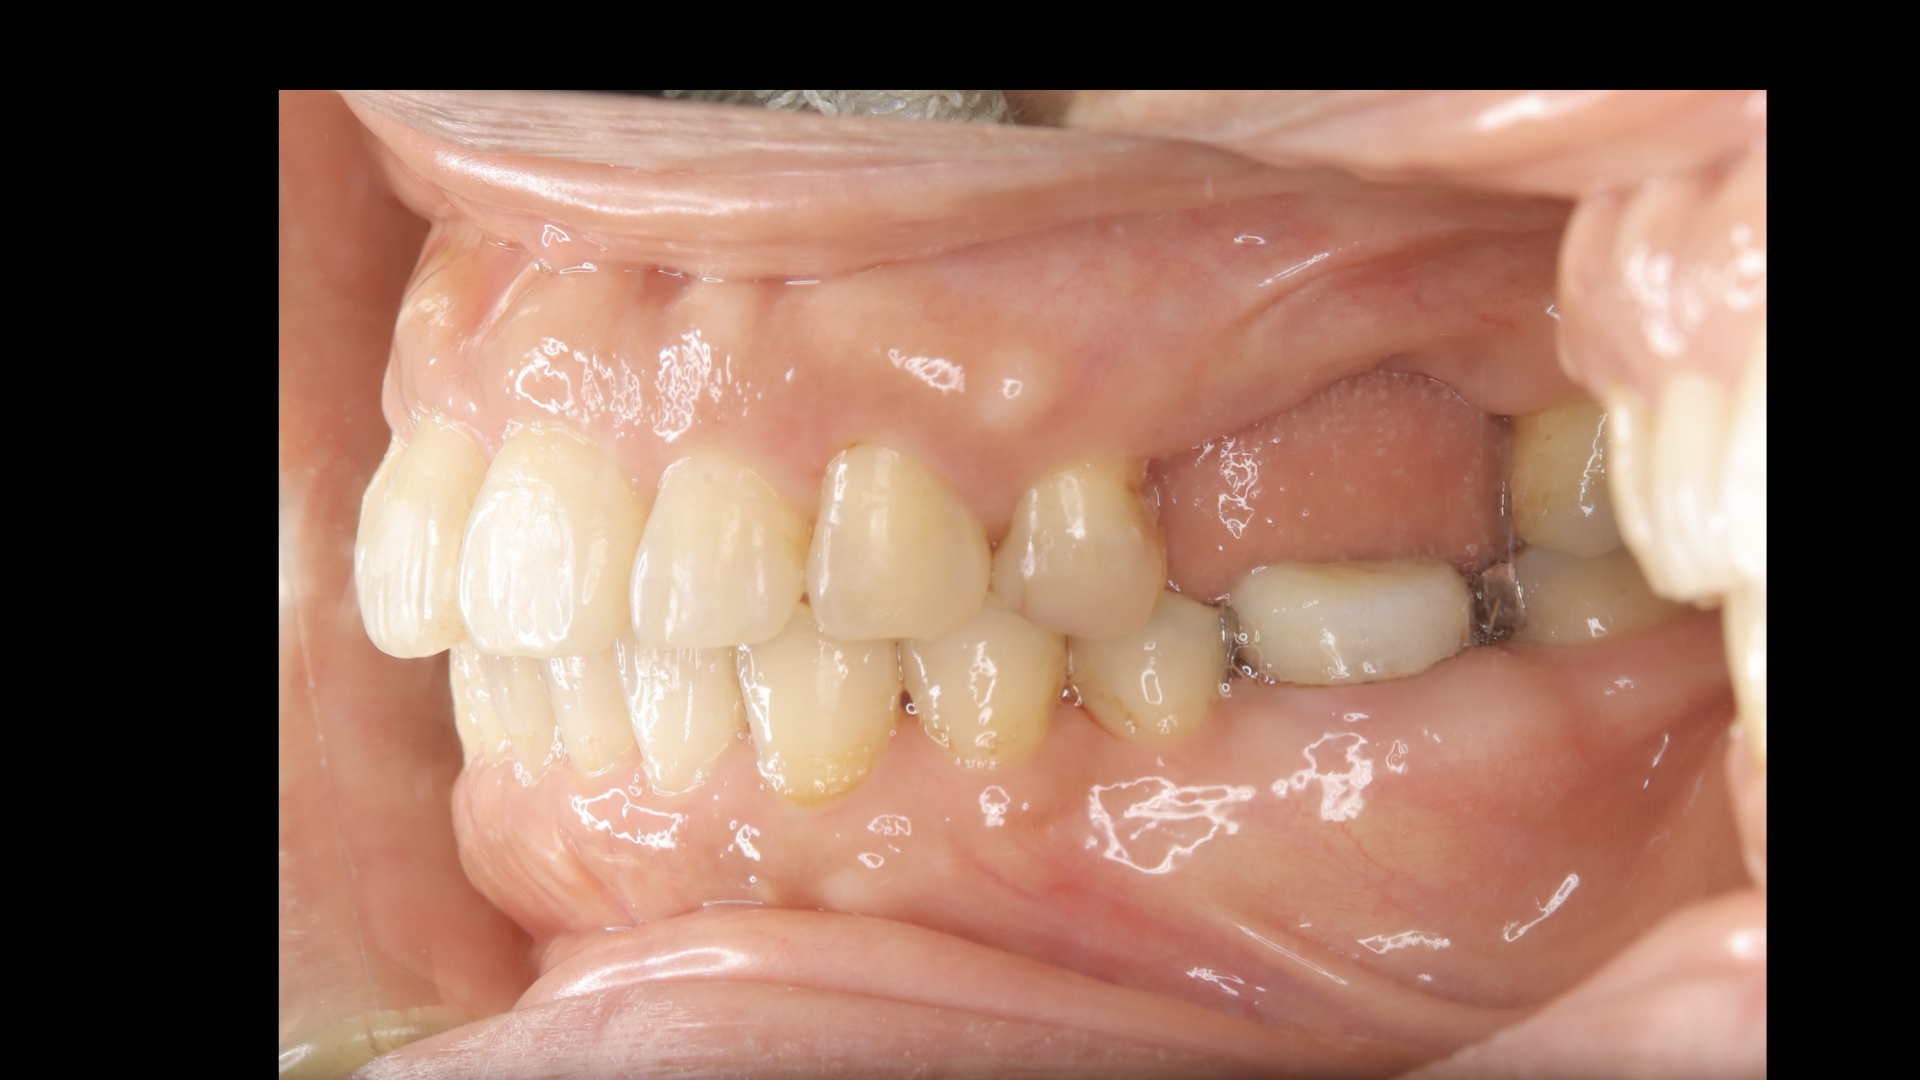

治療後の状態です。

前歯もしっかりと噛んでおりこれなら安心してインプラントを管理できます。

このように左側運動では左の犬歯(糸切り歯)だけが当たって、右側はあたらないように(離開:ディスクルージョン)

右側運動でも同じようになっており

治療前と違い、前歯が奥歯を守っている状態です。